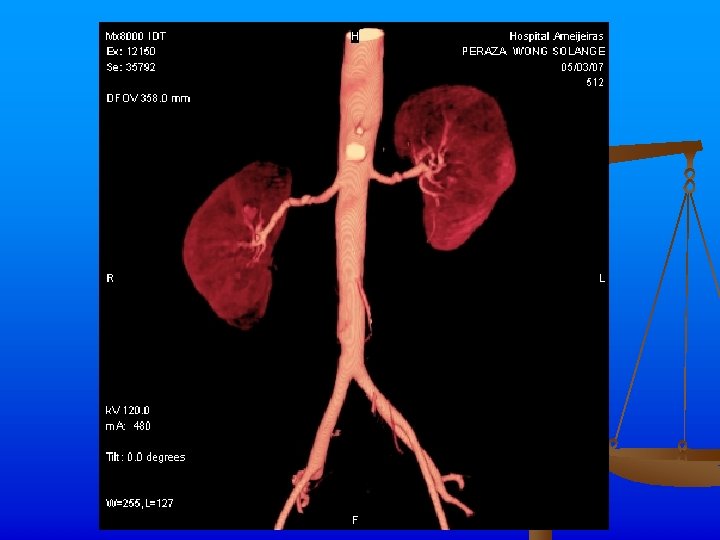

Exámenes Complementarios n n n Rx de tórax: Ligeros signos de hiperinsuflaciòn pulmonar. ICT normal. Índice de presiones de MI dentro de límites normales. Angio TAC: Se realiza angio. TAC abdominal inyectándose 120 ml de contraste, apreciándose áreas de estenosis y dilatación de ambas arterias renales, con un patrón arrosariado y zonas de hipoperfusión corticales en los polos de ambos riñones. Hay buena eliminación y concentración renal bilateral.